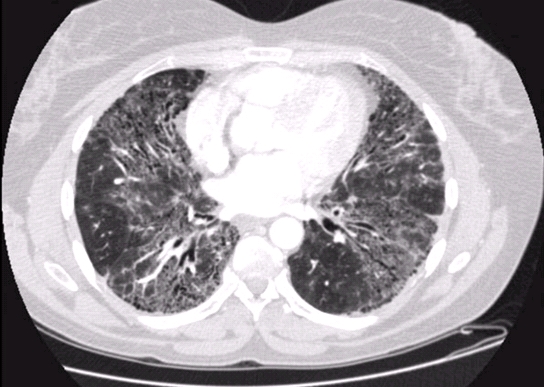

간이식 수술을 고려할 때, 이러한 환자들은

장기간의 간문맥압 항진증과 간위축 혹은 간비대증으로 인한 간의 혈관구조의 이상이 종종 발생할 수 있고,

그에 따른 수술 난이도가 매우 다양할 뿐만 아니라

심장 및 폐 기능 장애, 심한 근육 감소를 동반한 전신쇠약 등

다양한 합병질환을 가질 수 있기 때문에,

=서울아산병원을 찾는 간이식 수혜 환자들은,

국내 및 국제적으로도 유명한 타 간이식센터에 비해

특히 간문맥혈관 이상, Slavage(구제) 간이식, Budd-Chiari 증후군, 재이식 등과 같이

매우 난이도가 높은 간이식수술을 필요로 하는 빈도가 높습니다.

대표적으로 간문맥 협착 및 혈전증을 동반한 수혜자가 전체 간이식 환자의 20% 정도를 차지하고 있습니다.

성공적인 간이식이 되기 위해서는 수혜자의 병든 간을 제거후,

이식되는 간이식편으로 유입되는 문맥혈류가 잘 유지되는 것이 중요한데,

간문맥 협착이나 혈전증이 있는 경우에 간이식편으로 충분한 문맥혈류가

수술중 및 수술후에도 지속적으로 잘 유입될 수 있도록 해 주어야 합니다.

특히 중등도 이상의 간문맥 협착 및 혈전증이 있을 때,

문맥혈류가 잘 유지되어 성공적인 간이식이 될 수 있도록 하는 것이 매우 어려운데,

이 부분에서 우리 서울아산병원 간이식팀은

세계최초로 시행하는 수술방법들까지 고안하여 시행하고 있을 뿐만 아니라,

수술로도 미흡할 수 있는 부분에 대해선

수술중 영상의학과 중재시술팀과의 협업을 통해

국내 및 세계 어느 병원에서도 따라올 수 없는 독보적인 성공율로 간이식수술을 수행하고 있습니다.